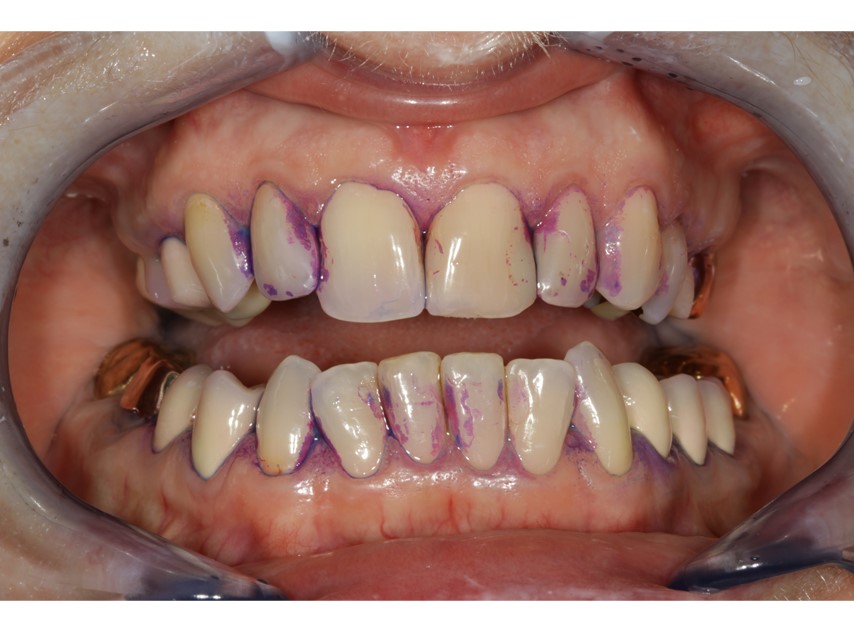

Eine Optimierung der häuslichen Mundhygiene durch den Patienten kann den Therapieerfolg positiv beeinflussen (12). Darum bietet sich zur Motivation der täglichen Selbstpflege die Aufnahme eines Mundhygienebefundes inklusive Mundhygieneinstruktion an. Für den Hausgebrauch können Handzahnbürsten wie auch elektrische Zahnbürsten empfohlen werden. Das Anwenden von Hilfsmitteln wie Interdentalraumbürstchen, Zahnseide oder spezielle Implantatseiden (Abb. 6 und 7) ist unbedingt erforderlich. Eine Implantatkonstruktion kann vergleichsweise zu natürlichen Zähnen vermehrt Plaqueretentionsstellen aufweisen – meist im Abutmentbereich.

Die Qualität der Prophylaxefachkräfte sollte in der Behandlung gewährleistet sein. Gemeinsam können sie mit dem Zahnarzt als überzeugendes Behandlerteam agieren, um eine hohe Patientenzufriedenheit in der UPIT zu erwirken. Das Verständnis des Patienten für die wiederkehrende Nachsorge muss erarbeitet werden. Die umfassende Beratung ist ein wirksames Instrument, ebenso erleichtern klare Praxisstrukturen die Patientenführung. Ein Beratungsgespräch mit PMPR vor der Implantation kann für den Patienten eine langfristige Vorstellung der Nachsorge schaffen. Ergänzend zur professionellen mechanischen Plaquereduktion sollten auch in jeder Sitzung Remotivationsgespräche und eine Mundhygieneinstruktion stattfinden (Abb. 8) sowie mögliche lokale und systemische Risikofaktoren erfasst werden. Bei Patienten mit unauffälligem Risikoprofil kann eine UPIT ein- bis zweimal im Jahr empfehlenswert sein, sobald Faktoren einfließen, ist die UPIT drei- bis viermal im Jahr anzuraten.